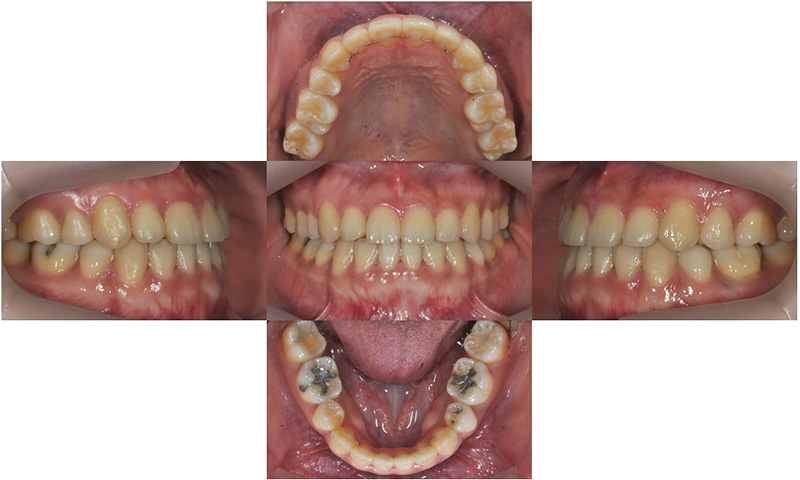

2019.5

약 17개월 동안의 교정 치료 마무리 후 사진으로, 치아 배열과 교합은 양호하게 개선되었으며, 정면 사진에서 부각되어 보이던 아래 입술 돌출도 개선되어 어려보이는 인상을 가지게 되었습니다.